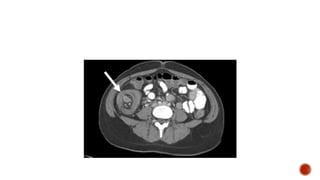

CT SCAN

However, CT cannot be used to reduce the intussusception and can

be time-consuming in children who may require sedation. Thus, CT

generally is reserved for patients in whom the other imaging

modalities are unrevealing, or to characterize pathological lead

points for intussusception detected by ultrasound.

CT SCAN However, CTcannot be used to reduce the intussusception and can be time-consuming in children who may require sedation. Thus, CT generally is reserved for patients in whom the other imaging modalities are unrevealing, or to characterize pathological lead points for intussusception detected by ultrasound.